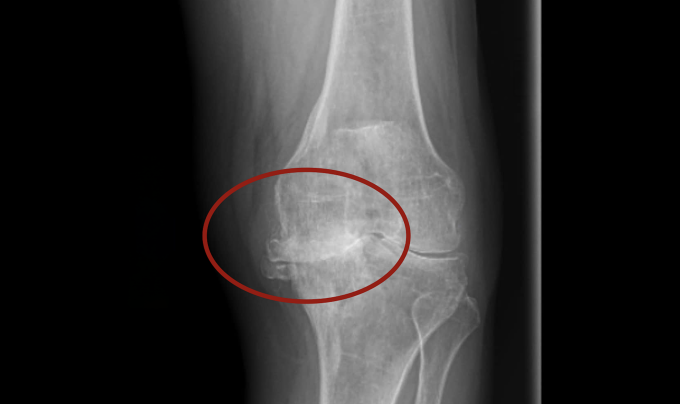

Gần đây,khớp càng sưng đau,bà đến Bệnh viện Đa khoa Tâm Anh TP HCM chụp X-quang cho thấy khớp gối trái thoái hóa giai đoạn cuối,biến dạng nặng,vẹo trục 15 độ,mất hết sụn,tổn thương xương dưới sụn,mất xương mâm chày bên trong. Người bệnh còn bị suy giảm chức năng gan thận,dẫn đến suy thận mạn giai đoạn sớm,bác sĩ Học cho rằng "do bệnh nhân tự ý dùng nhiều thuốc trong thời gian dài".

Kết quả chụp X-quang cho thấy khớp gối của bà Hồng tổn thương nghiêm trọng,các đầu xương va chạm trực tiếp vào nhau. Ảnh: Bệnh viện Đa khoa Tâm Anh